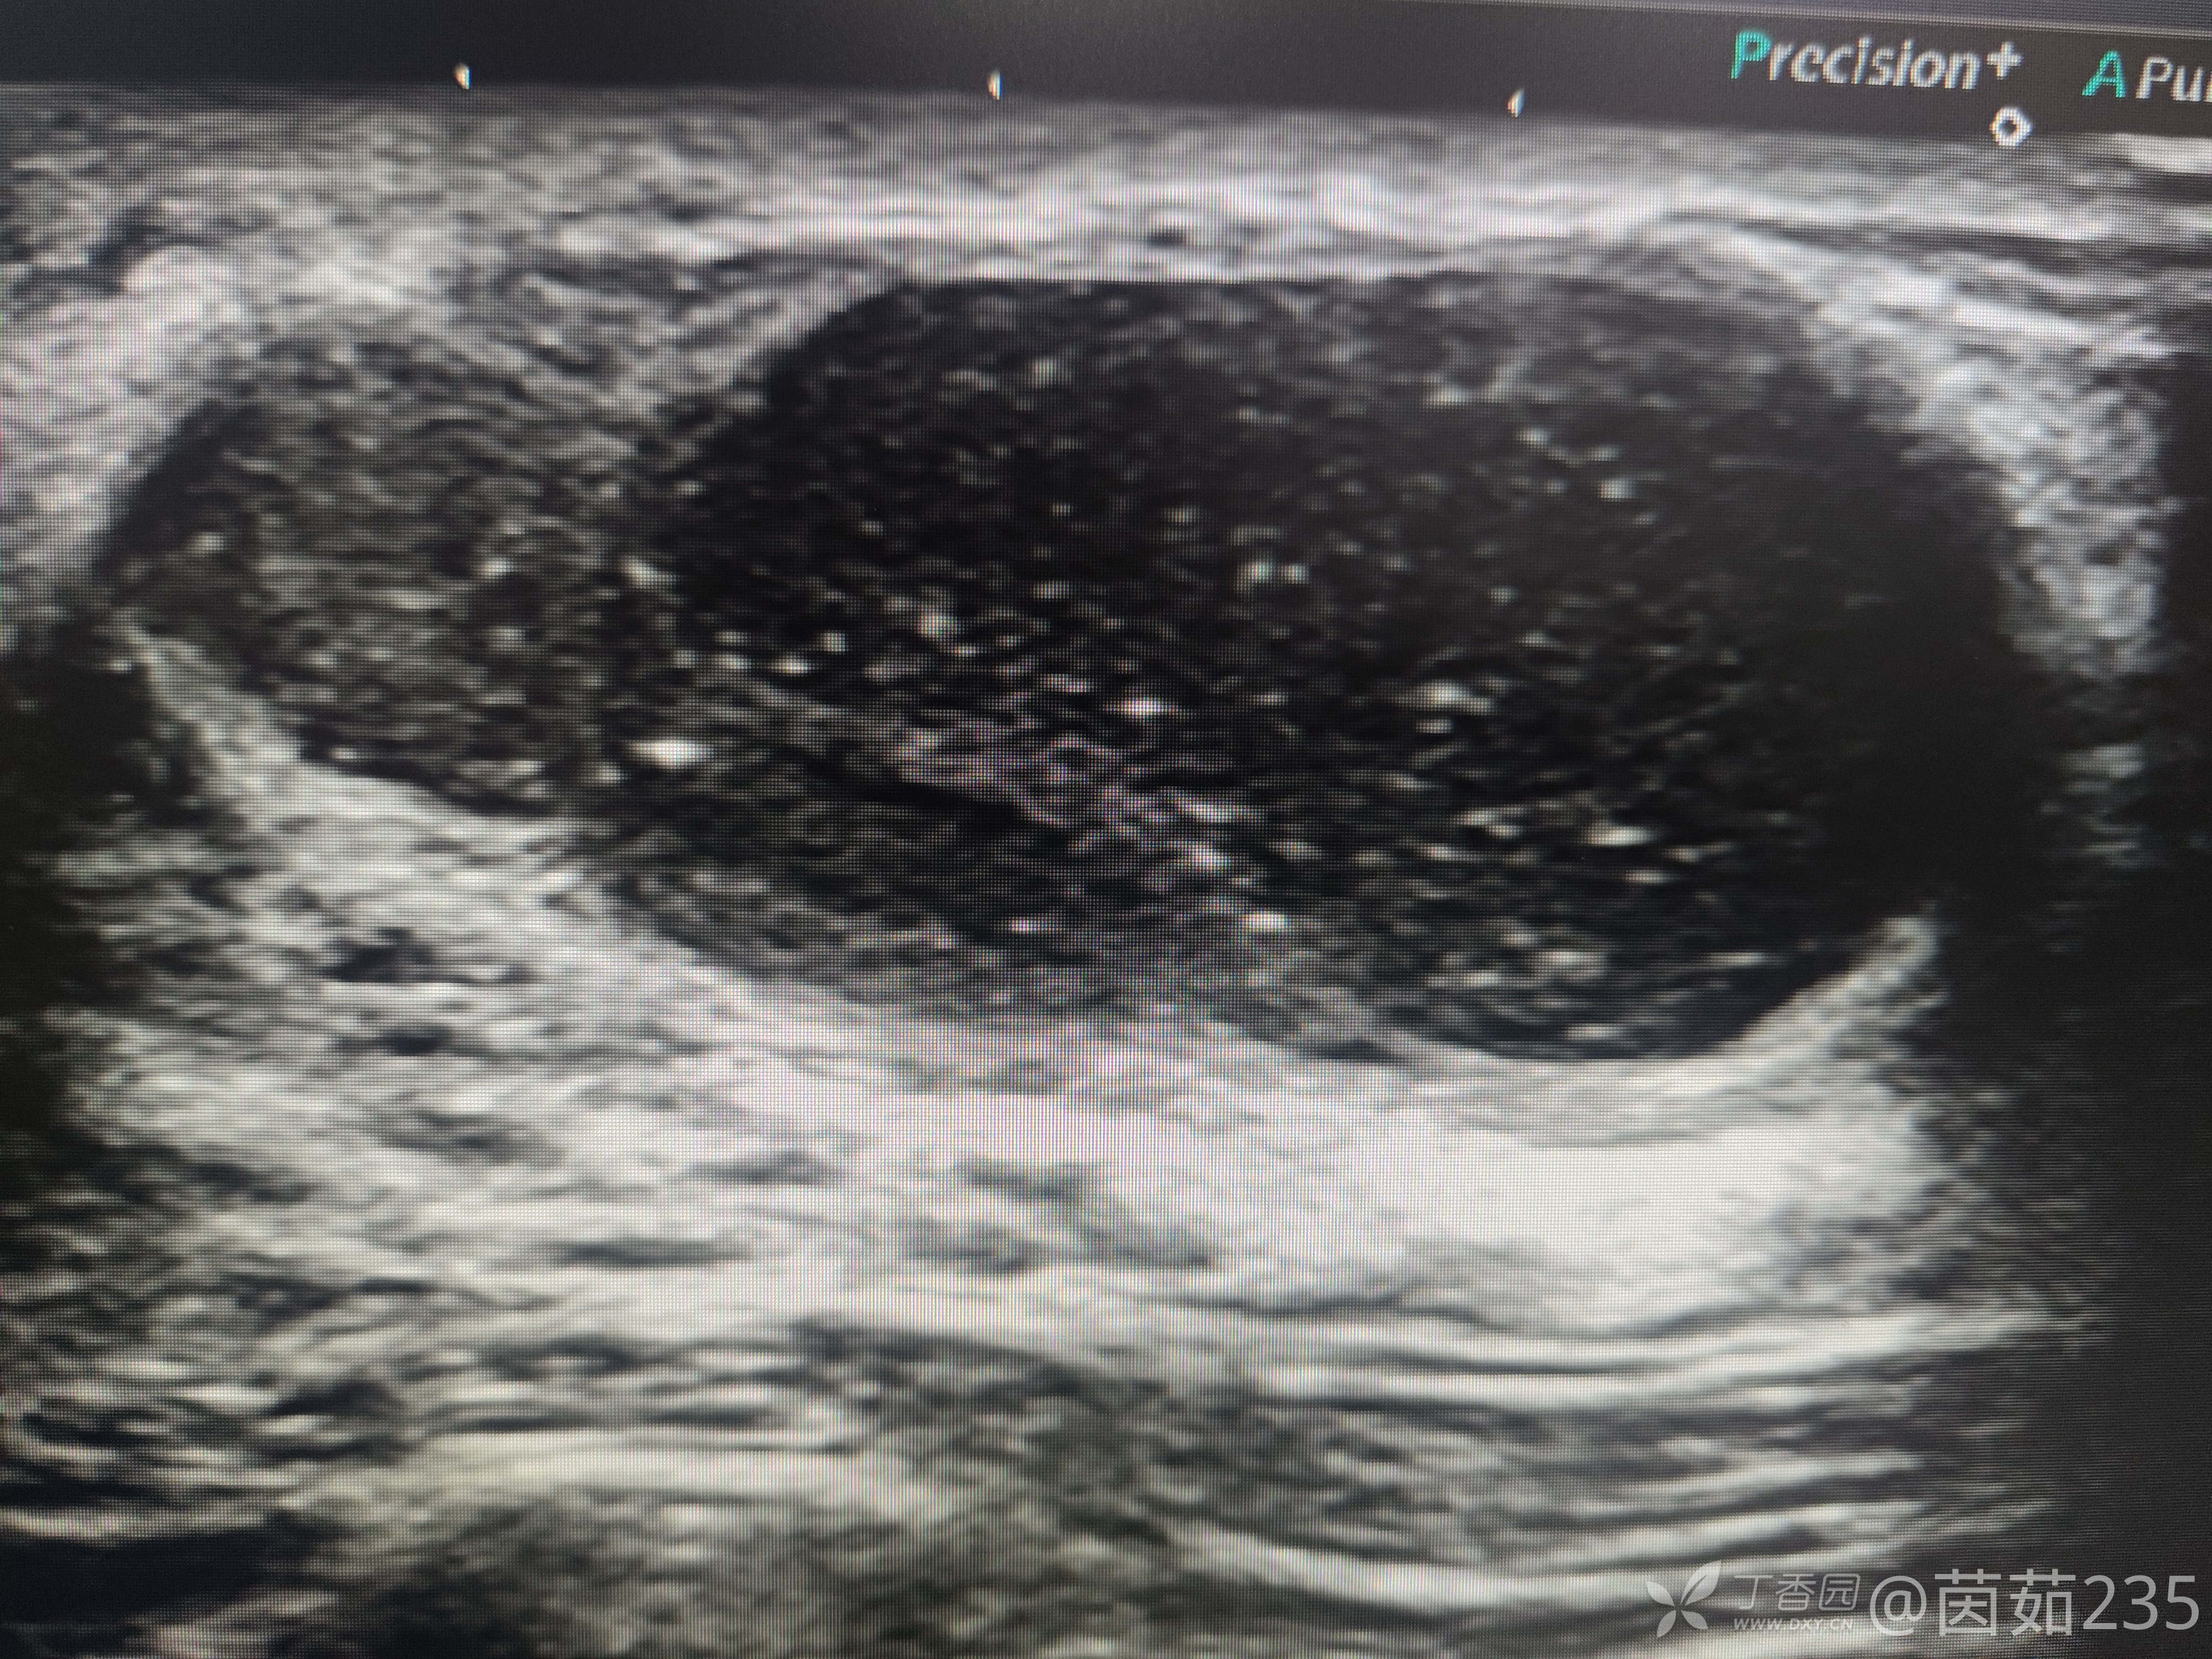

右侧乳腺12点乳晕后方腺体内可见一低回声包块,大小37✖️16mm,边界清,壁厚,内回声不均,可见数个彗星尾。来看看图,你们觉得该分几类?考虑是什么?